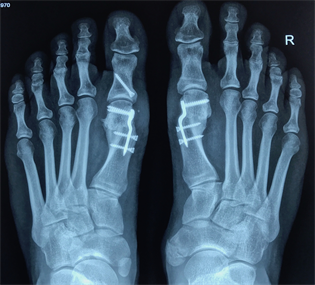

Figure 18. Patient Nr. 4. Bilateral moderate hallux valgus.

Figure 19. Patient Nr. 4. Side view left foot.

Figure 20. Patient Nr. 4. Side view right foot.

Figure 21. Patient Nr. 4. 5 years after bilateral correction. Outpatient. Immediate full weight bearing.

Figure 22. Patient Nr. 4. Side view of the left foot shows the plantarization of 2 mm.

Figure 23. Patient Nr. 4. Side view of the right foot shows the plantarization of 2 mm.

Figure 24. Patient Nr. 4: Preoperative clinical view.

Figure 25. Patient Nr. 4: Postoperative clinical view.

Figure 26. Patient Nr. 4: Postoperative clinical view.